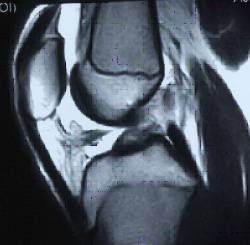

Els traumatismes rotacionals amb vessament articular i la presència de sang són indicatius de la possible lesió del lligament creuat anterior.

És important considerar que la base del diagnòstic és clínic, basant-nos en l’anamnesi i l’exploració clínica.

Les exploracions complementàries poden no coincidir amb el diagnòstic clínic i es poden arribar a donar fins a un 40% de falsos negatius segons les sèries publicades.